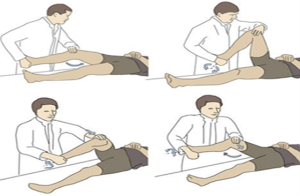

تست های تشخیص پارگی منیسک زانو :

- یک روش رایج برای بررسی این نوع پارگی، تست مک موری است. پزشک و یا فیزیوتراپیست از شما می خواهد که روی تخت دراز بکشید. آنها زانوی شما را خم می کنند و صاف می کنند و آن را در هر دو طرف می چرخانند. اگر در منیسک خود پارگی داشته باشید، ممکن است احساس درد کنید یا صدای کلیک در مفصل بشنوید.

تصویر شماره سه : نحوا انجام تست مک موری